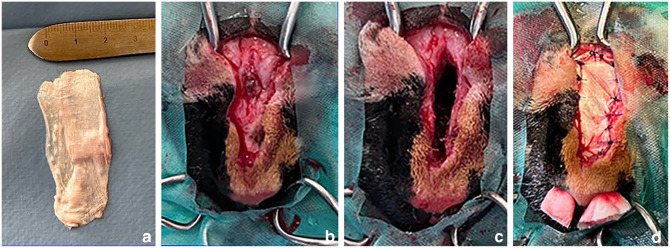

病例摘要:一只 6 岁的雌性绝育短毛猫在 7 个月前出现鼻背皮下肿块。CT 检查显示该猫存在鼻腔皮样窦囊肿和鼻骨缺损。手术切除了囊肿,并采用自体筋膜移植进行重建。鼻背骨得到了重建,长期结果显示呼吸功能没有受到影响。两周随访时未发现短期并发症。在 2 个月和 12 个月的随访中未发现长期并发症或复发。在猫鼻腔皮样窦囊肿手术切除后,筋膜移植似乎是修复鼻骨缺损的有效方法。这种方法成本低廉,组织易于采集,并能提供良好的功能和外观效果:据作者所知,这是第一份评估使用自体筋膜移植修复猫鼻皮样窦囊肿切除术后鼻骨缺损效果的报告。

Case summary: A 6-year-old female spayed domestic shorthair cat was presented with a 7-month history of a subcutaneous mass on the dorsal nasal surface. A CT examination revealed the presence of a nasal dermoid sinus cyst with a nasal bone defect. The cyst was excised and an autologous fascia lata graft was used for reconstruction. The dorsal nasal bone was reconstituted and no compromise of respiratory function was reported in the long-term outcome. No short-term complications were observed at the 2-week follow-up. No long-term complications or recurrence were observed at the 2- and 12-month follow-ups. Fascia lata grafting appears to be an effective method for repairing a nasal bone defect after surgical excision of a nasal dermoid sinus cyst in cats. It is inexpensive and the tissue is easily harvested and provides good functional and cosmetic results.

Relevance and novel information: To the authors' knowledge, this is the first report that evaluates the effectiveness of repairing a nasal bone defect after dermoid sinus cyst excision in a cat using an autologous fascia lata graft.